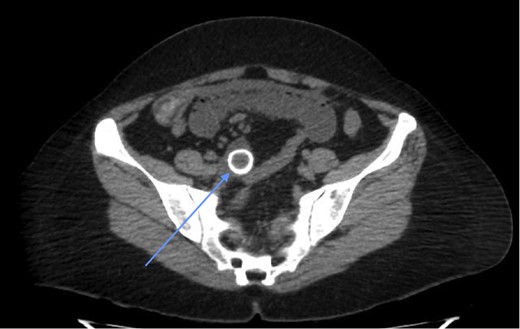

Laboratory investigations (biochemical profile and urinalysis) were all within normal limits. Abdominal CT showed pneumobilia and a 2 cm intraluminal density in the distal ileum with resultant small bowel obstruction (Figs 1 and 2). She underwent emergency laparotomy and enterolithotomy followed by a smooth postoperative course (Figs 3 and 4). The CT scan taken elsewhere and just prior to the emergency cholecystecomy 12 months earlier was reviewed; this demonstrated a markedly distended gallbladder with irregular wall thickening and severe pericholecystic fat stranding consistent with a gallbladder empyema measuring 16 cm × 9.0 cm. There were also multiple gallstones with the largest two measuring 2 cm at the neck of the gallbladder and the other, 2.0 cm in diameter at the fundus of the gallbladder, respectively. There was a narrower, septum-like area between the neck and grossly distended empyema (Fig. 5)

CT scan showing a rim-calcified gallstone, causing ileal obstruction.